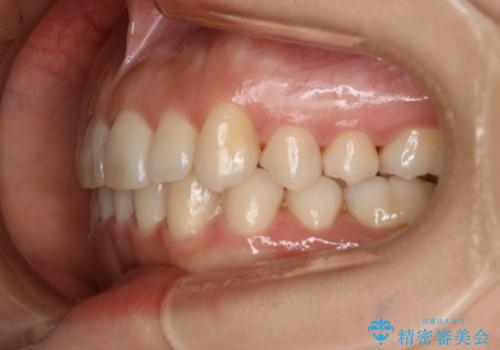

下顎については、前歯にがたつきがありました。

下顎については、歯の側面を削ることをメインにがたつきを改善しました。

今回、奥歯のかみ合わせに問題がなく、前歯のがたつきのみの対応だったため、インビザライン モデレートというものを使用しました。インビザライン モデレートは歯を動かせる枚数が、最大26枚までと制限があります。お口の中の状態をよく精査し、どの種類のインビザラインを使用するかを判断しています。